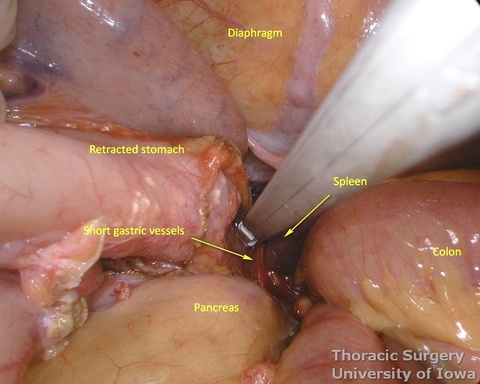

- Divide short gastric vessels with an energy device with care to avoid traction injury of the spleen.

- Fundus of the stomach is dissected free all the way to the esophageal hiatus dividing gastro-phenic ligament and remaining adhesions.